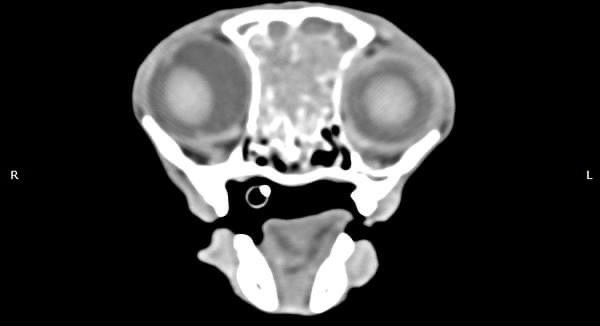

• 貓咪 鼻腔腫瘤腺癌 Adenocarcinoma

貓咪 鼻腔腫瘤腺癌 Adenocarcinoma

• 狗狗 鼻腔腫瘤 惡性上皮癌

狗狗 鼻腔腫瘤 惡性上皮癌